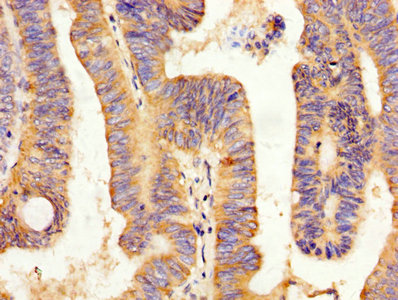

IHC image of CSB-PA12214A0Rb diluted at 1:200 and staining in paraffin-embedded human small intestine tissue performed on a Leica BondTM system. After dewaxing and hydration, antigen retrieval was mediated by high pressure in a citrate buffer (pH 6.0). Section was blocked with 10% normal goat serum 30min at RT. Then primary antibody (1% BSA) was incubated at 4°C overnight. The primary is detected by a biotinylated secondary antibody and visualized using an HRP conjugated SP system.